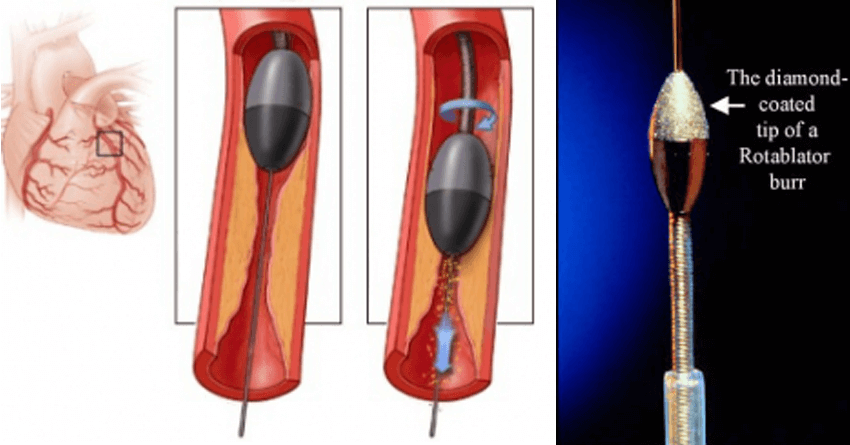

While the blockages in the younger individuals are easy to dilate using the balloon, owing to the softer nature of the block, it is less likely to remove the blockages with similar ease in the elderly. These blocks are relatively difficult to negotiate because of a hard matrix containing calcium and other natural salts in addition to fat. The harder blocks, which cannot be dilated using balloon before deployment of the stent due to calcium deposition, need Rotablation, an interventional tool for debulking the harder lesions.

Rotablator burr: A special catheter, with an acorn-shaped, diamond-coated tip, is guided to the point of narrowing in your coronary artery. The tip spins around at a high speed and grinds away the plaque on your artery walls